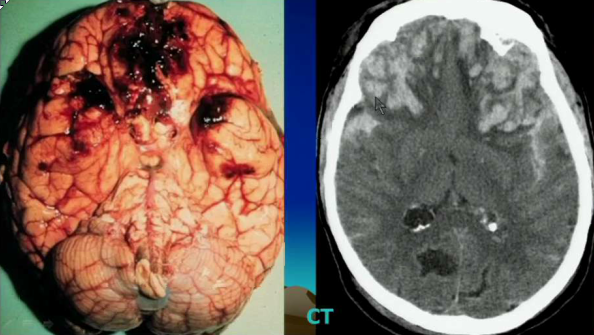

What is the most commonly injured cranial nerve in TBIs?

CN I. Patients will complain of things tasting weird because it controls 75% of taste.